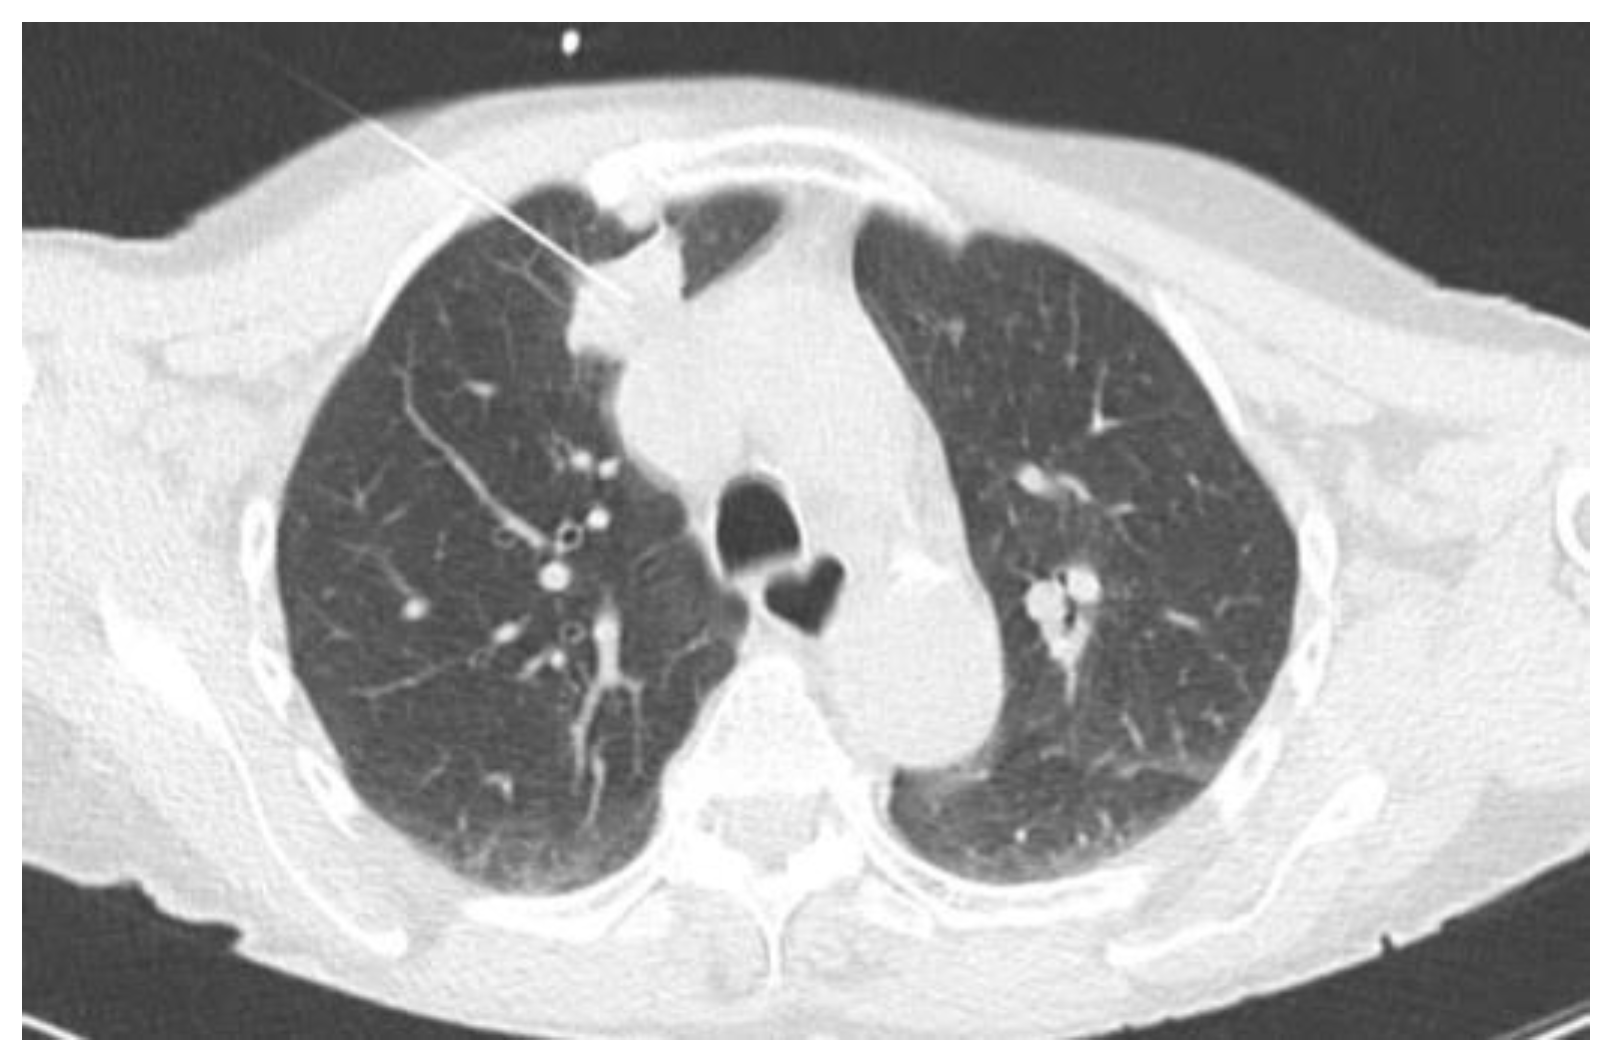

2.2.1. TIME 0: Lesion marking and SPECT Analysis

| Site of lung cancer | LUL | RLL | RUL | LLL | RUL | RUL | LUL | RUL |

| Clinical stage | IB | IB | IB | IA | IA | IB | IB | IB |

| Site of Lung Cancer | Histotype | SPECT-Positive SLN Station | Intraoperative Positive SLN Station | |

|---|---|---|---|---|

| Patient 1 | LUL | ADC | 10 | 10 |

| Patient 2 | RLL | ADC | * | 9 |

| Patient 3 | RUL | ADC | 11 | 11 |

| Patient 4 | LLL | ADC | # | 11 |

| Patient 5 | RUL | ADC | # | 4 |

| Patient 6 | RUL | ADC | 10 | 10 |

| Patient 7 | LUL | SCC | * | 5 |

| Patient 8 | RUL | ADC | 10 | 10 |